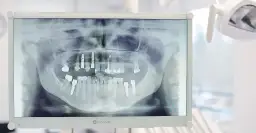

Jeśli mleczak wypadł, a ząb stały nie pojawia się przez kilka miesięcy, to sygnał, że warto umówić się na wizytę u stomatologa dziecięcego. Czasami zawiązek zęba stałego jest obecny, ale ma nieprawidłowe ułożenie lub po prostu potrzebuje więcej czasu. W innych przypadkach może się okazać, że zawiązek zęba stałego w ogóle nie powstał. Dentysta zazwyczaj zaleci wykonanie zdjęcia RTG, aby sprawdzić obecność i położenie zawiązka zęba stałego oraz podjąć odpowiednie kroki, jeśli to konieczne.